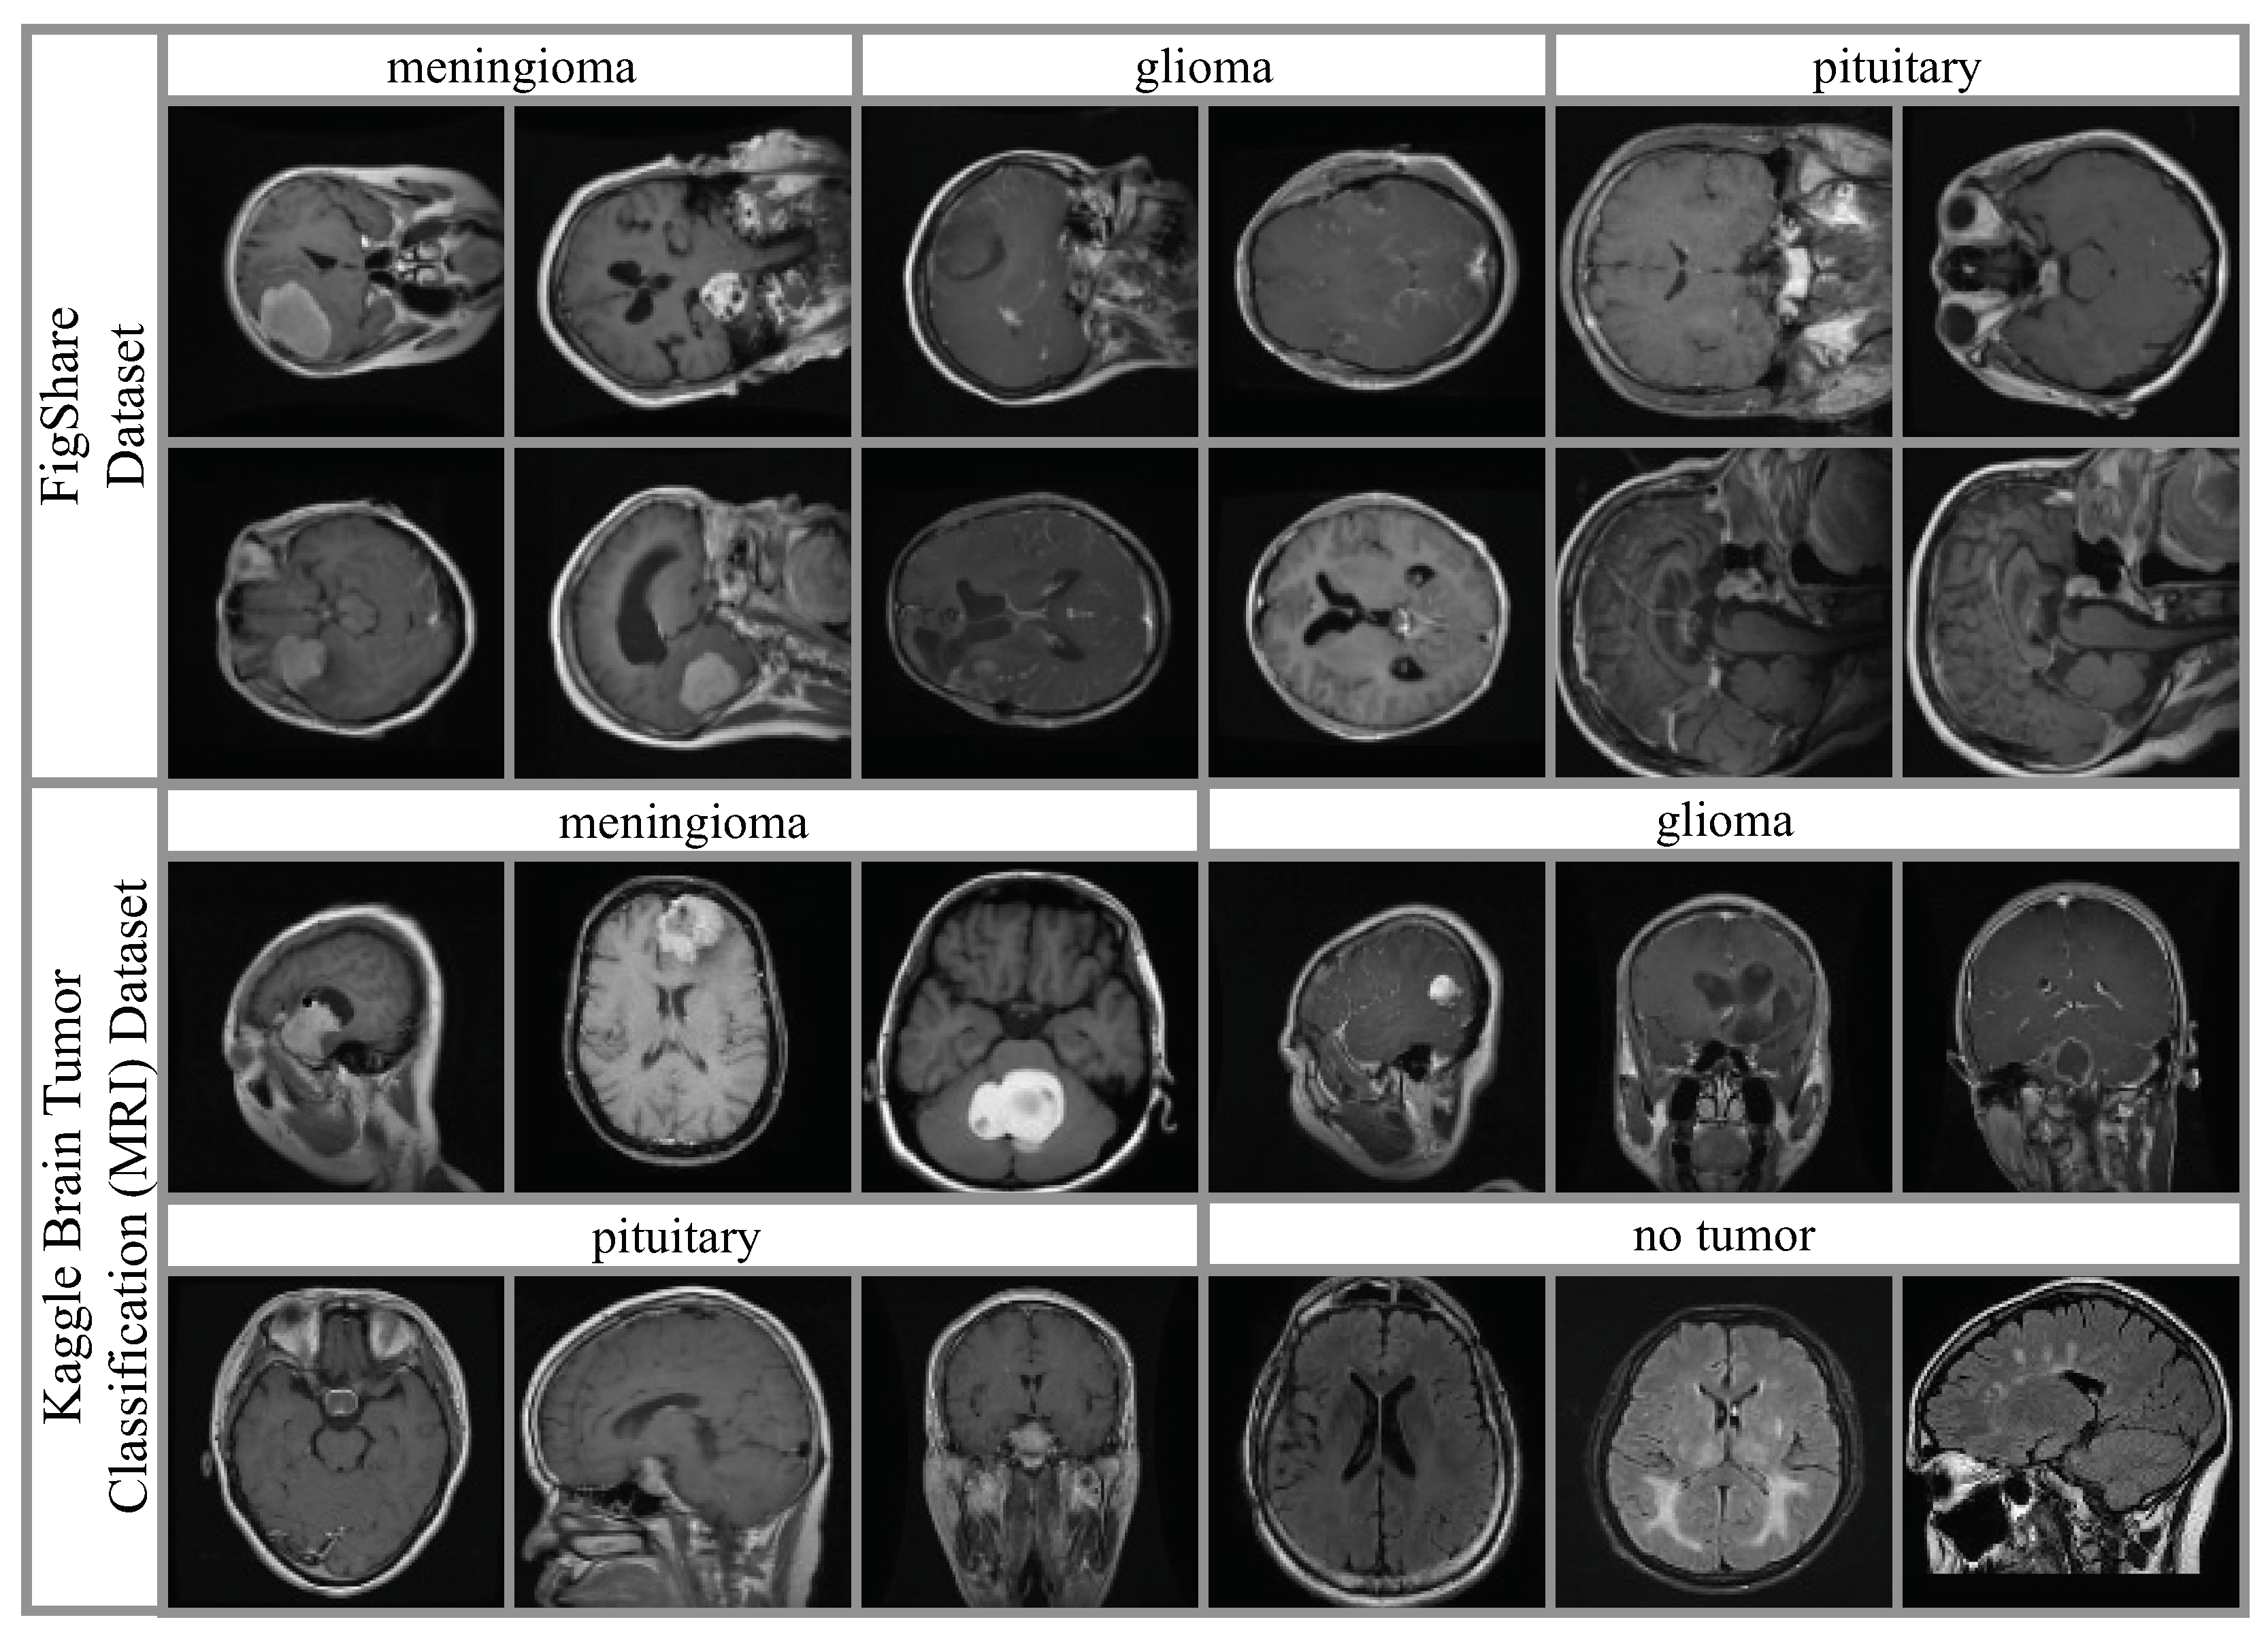

4.1. Datasets and Hyperparameter Settings